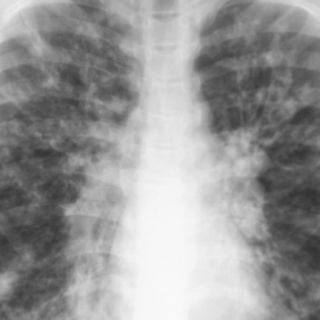

Esta enfermedad causa una acumulación de mucosidad viscosa en los pulmones y otros órganos

La fibrosis quística causa una acumulación de mucosidad viscosa en los pulmones y otros órganos, lo cual provoca infecciones, trastornos digestivos y la muerte a edad temprana. La esperanza de vida típica del paciente es de 37 años, según la Fundación para la Fibrosis Quística.